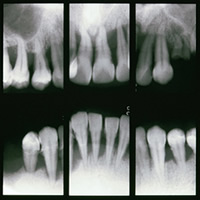

中等度歯周炎

歯周治療の必要があります。歯を支える骨がなくなってくると歯が動きだします。

だんだんと治療も難しくなってきます。 |